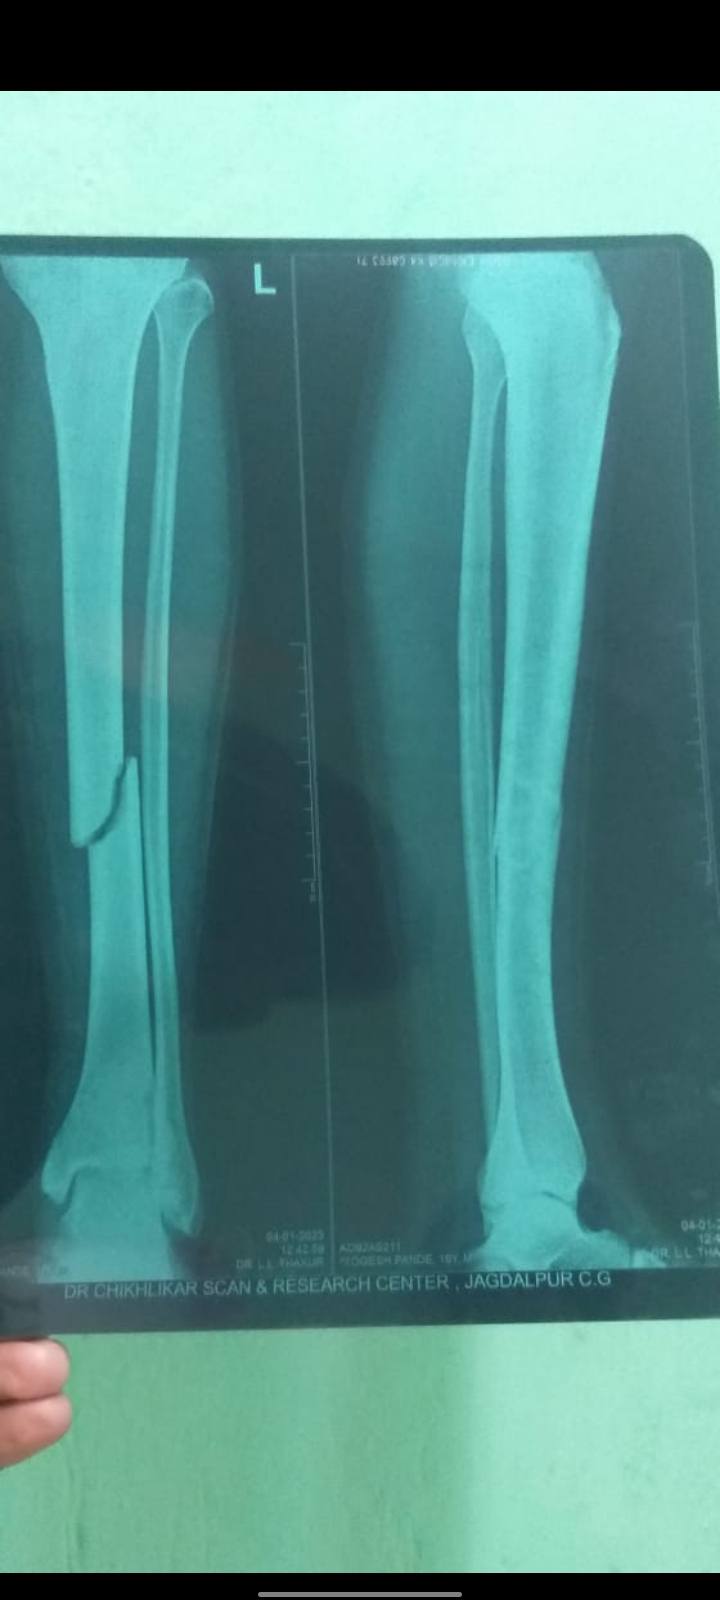

Yogesh Pandey